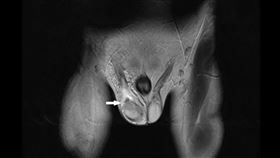

罕見「睪丸梗塞」險奪命 醫即刻救援高中生

「心肌梗塞」急速奪命大家常聽到,但「睪丸梗塞」相對就...